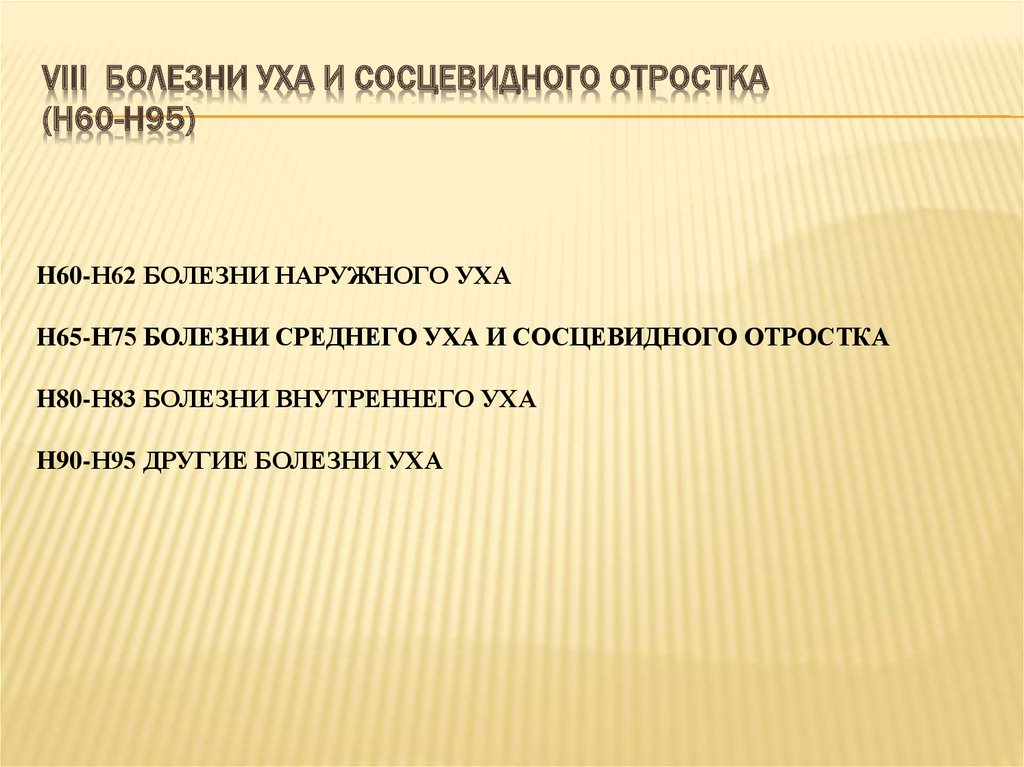

Код мкб 10 атерома головы

Код мкб 10 атерома головы 109 фото